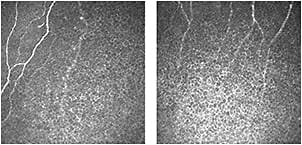

Confocal Microscopy—Rostock Cornea Module on HRT III

More recently, Heidelberg Engineering GmbH developed a digital confocal laser scanning microscope, a combination of Heidelberg Retina Tomograph III and the Rostock cornea module (RCM). The RCM images cellular structures and can image the different layers of the entire cornea, from the epithelium to the endothelium. The RCM also enables the imaging of the peripheral areas of the cornea and conjunctiva (Figure 10). The instrument allows a focal range of up to 1,500µm with a field of view of 400µm x 400µm. This instrument offers three capture modes:

Figure 10. Confocal microscopy images of the cornea. The corneal nerves are visible in both scans. (Images provided by the CCLR, University of Waterloo.)

The charge-coupled device (CCD) camera allows a permanent monitoring of the corneal contact on the screen. The RCM technology provides better image quality and produces a precise depth measurement compared with confocal-slit scanning microscopes.